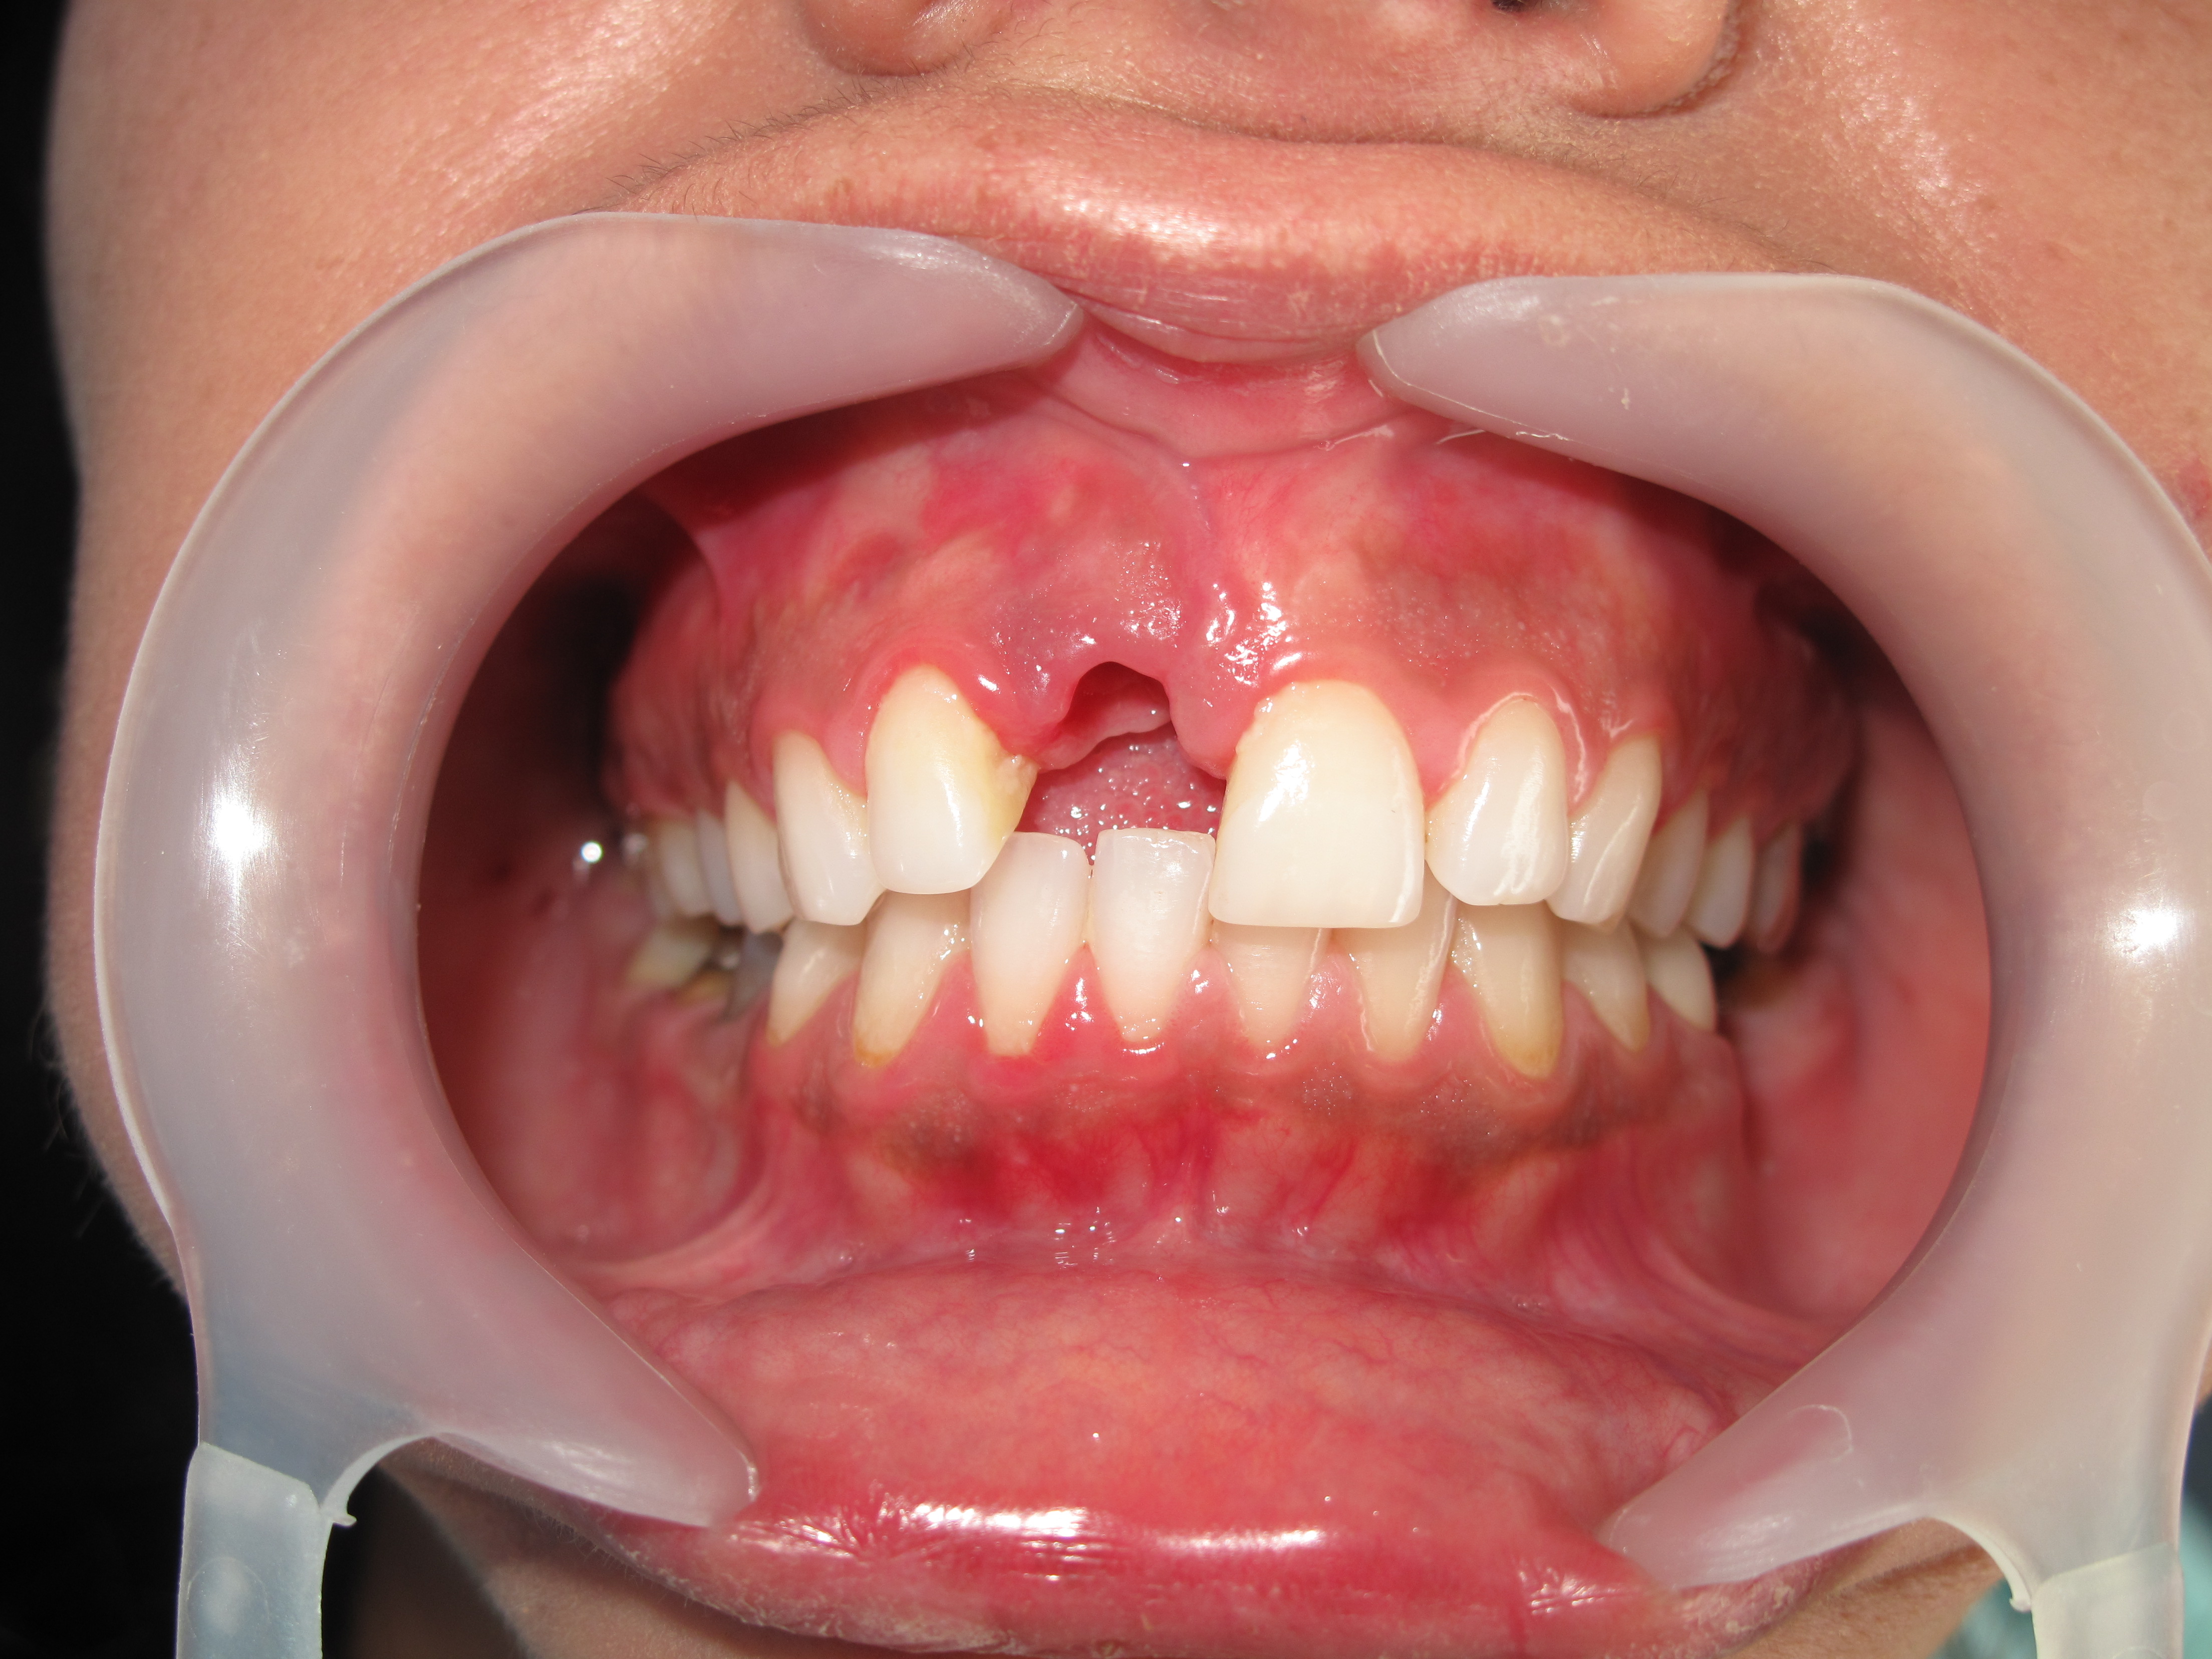

Dental implants are most difficult in the esthetic zone especially when it needs Bone graft management.